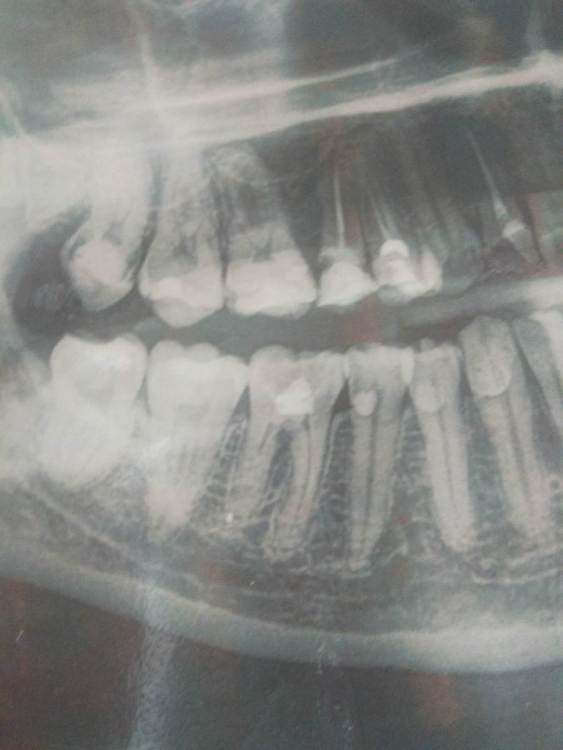

Primavera2023 Опубликовано 27 октября, 2023 Поделиться Опубликовано 27 октября, 2023 (изменено) Здравствуйте. Мне 32 года. 11 лет назад залечили пульпит нижней правой 6, как потом выяснилось резорцин - формалином. Узнала только недавно. До этого никто из стоматологов не мог объяснить красновато- коричневый цвет эмали пришеечной части зуба. Говорили, просто патологическая стираемость. Десна первое время болела, потом прошла. Вскоре десна возле зуба стала серого оттенка. И навсегда увеличился лимфоузел на шее справа. Узнала, что эта паста вредна как местно, так и для всего организма и что такой зуб может быть очагом хронической инфекции. Да и сама пломба на зубе очень заметная. Насколько сложно будет перелечить этот зуб с нормальной пломбировкой каналов? Нужно ли обязательно искать врача с микроскопом и коффердамом, так как это будет дороже? Большой ли риск потерять зуб в процессе повторного эндодонтического лечения? Простоит ли зуб дольше, если его перелечить? И можно ли будет не ставить коронку, а повторно закрыть световой пломбой? Меня смущает, что на снимке часть канала справа замурована дентином. Прочитала, что это может говорить о том, что резорцин-формалиновая паста при пломбировке попала на ещё живую пульпу и теперь в этой части канала "стекло", пройти которое проблематично, а порой и невозможно. И можно ли будет там не проходить, если врач не сможет? Зуб не беспокоит, кроме небольшого эстетического дефекта. Беспокоит серый цвет десны возле него. Изменено 27 октября, 2023 пользователем Primavera2023 Ссылка на комментарий

Doc Опубликовано 28 октября, 2023 Поделиться Опубликовано 28 октября, 2023 На большую часть вопросов ответить сможет врач только после того, как вскроет зуб и попытается залезть внутрь. По идее, такой зуб нужно перелечить, но после резорцина это не всегда удается. Удастся или нет конкретно в данном случае, покажет только вскрытие. Но у вас есть еще 15 зуб, с которым проблем не меньше, если не больше. Возможно, и другие зубы требуют перелечивания. Но все это по одному снимку не скажешь. 1 Ссылка на комментарий

Primavera2023 Опубликовано 28 октября, 2023 Автор Поделиться Опубликовано 28 октября, 2023 (изменено) Спасибо за ответ! Попробую переделать Боюсь, как бы совсем без зуба не остаться. Если я правильно поняла, серый оттенок десны связан с тем, что окрашенные корни зуба просвечивают через неё, а не с некрозом, о чём я подумала вначале. В 15 девитальном зубе частичное разрушение коронковой части возле пломбы? Там мне в 2016 году лечили периодонтит через десну и вводили какой-то композит. Был открытый свищевой ход. Зуб шатался, предлагали удалить. Но потом укрепился и больше не беспокоил. Изменено 28 октября, 2023 пользователем Primavera2023 Ссылка на комментарий